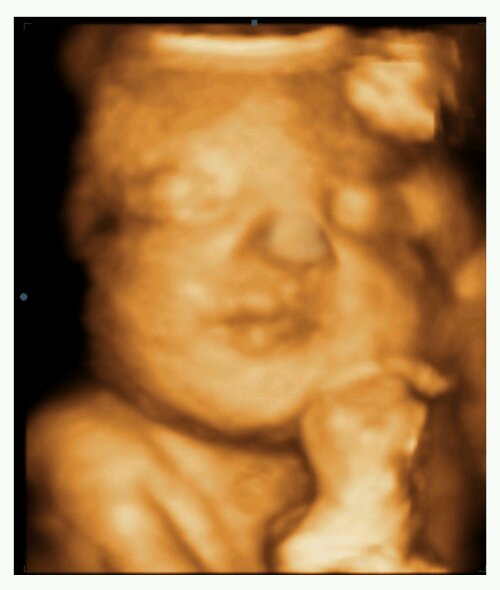

I awoke this morning from a dream in which I was holding Nora. This was the first time I’ve dreamt of holding her (that I can remember). As with all of my pregnancies, I logically know there is a baby in there, but it isn’t until I am actually holding that new little life that I really fully comprehend the great, unimaginable, unconditional love between a parent and child. There is nothing like it. That blinding love was right there in my dream. My cheek rested on her soft little head and all was right with the world in that very moment of blissful happiness.